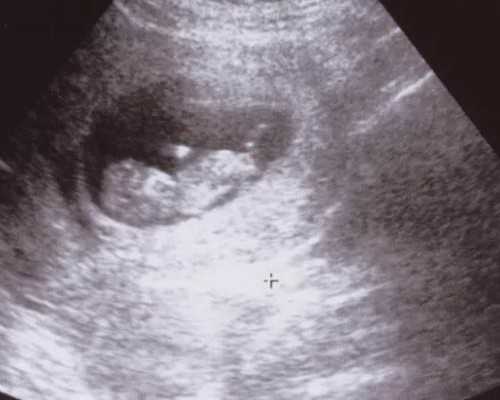

香港验血,大家都知道,是测宝宝是男是女的,在怀孕50天以上就能测出来,测的时候是抽手臂上的血,大概12ML左右吧,小玻璃管,跟我们平常去医院做血常规抽血一样,抽完就可以走了,结果是隔天出来的,不过呢,去香港验血之前要提前一两天预约好再去哦。

预约很简单,预约是免费的,预约的时候要提供B超单,建议53天左右再去做B超,因为有些姐妹怀孕的时候,胚芽长得比较慢,50天了还不到10毫米,所以建议再等个两三天再去B超,够10毫米了才能预约去香港验血。

香港验血的条件非常严格的,除了胚芽要求达到10毫米以上,还有另外几个条件,如:一年内没生过男孩、半年内没有流产过、没有重大手术、输血、器官移植,满足以上条件,那你验血的准确率高达99.4%以上。

其实鉴定宝宝性别的方式主流的有两种,一种是B超,一种是验血基因检测,基因检测是后面才流行起来的,原因其实就在于验血的准确率更高,基本上能达到98%左右。比如香港时代基因检测中心,准确就能达到99.8%以上。